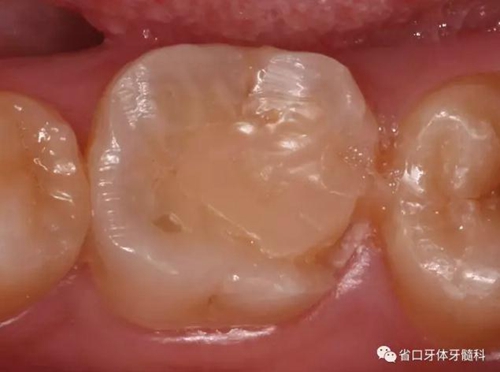

檢查:46牙合面牙色充填物,叩+,松I度,探及頰舌側(cè)根分叉處牙周袋深及根尖區(qū),頰側(cè)牙齦略腫脹。

圖1 初診X片示根尖周及根分叉大范圍低密度影像